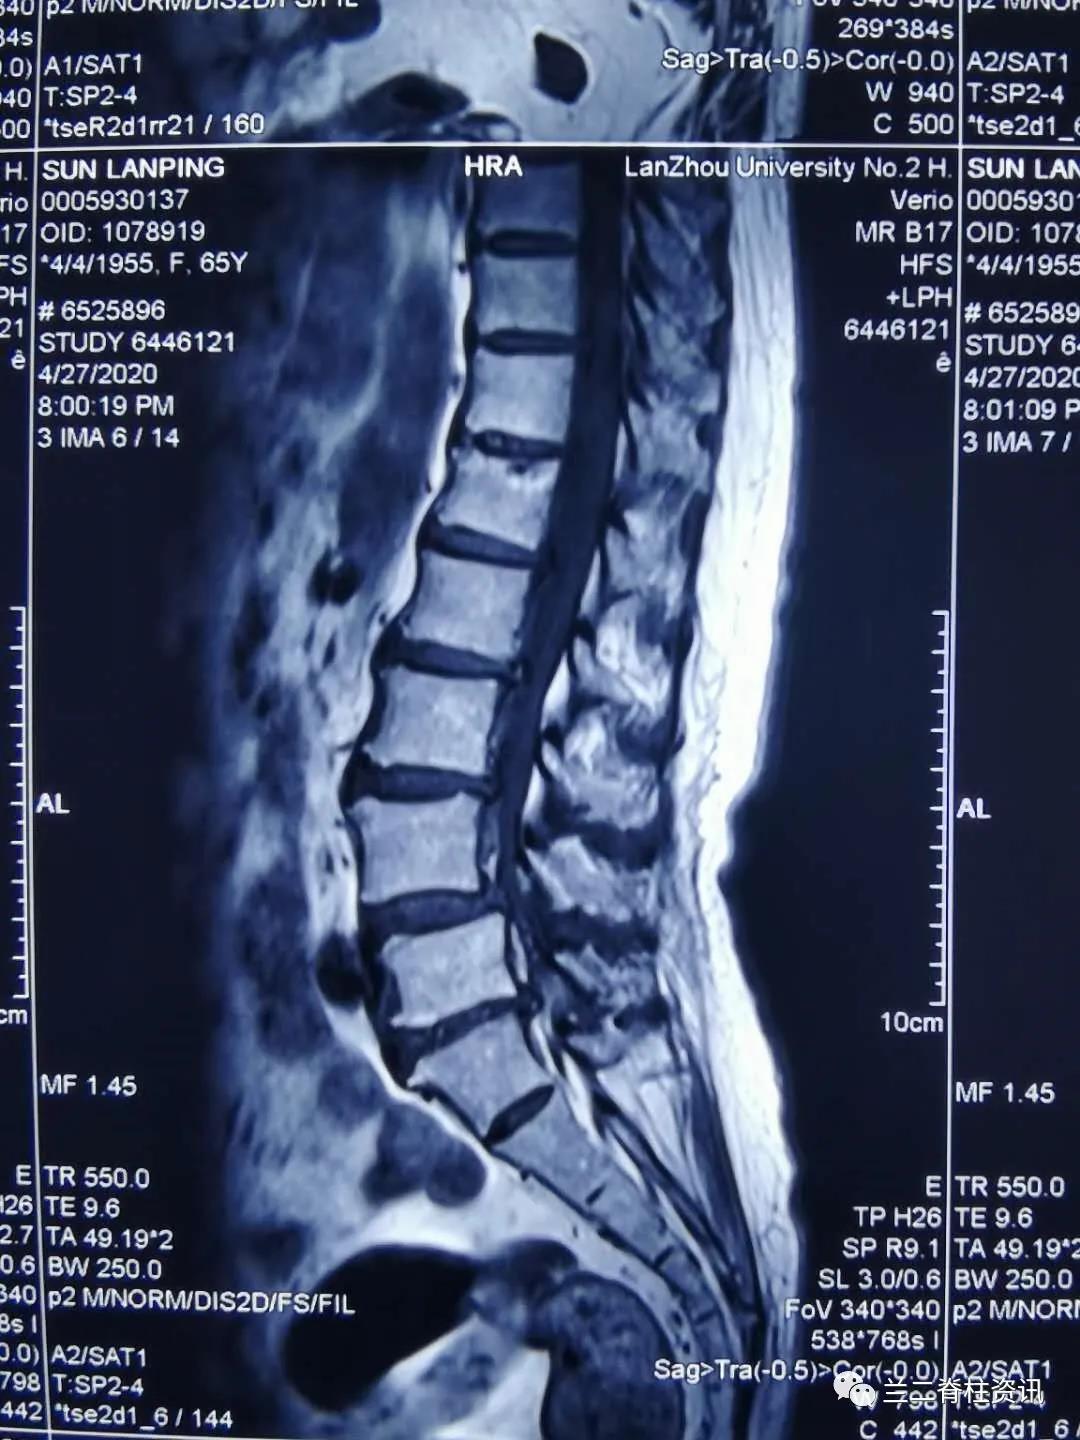

患者,女性,65岁,因“腰痛伴双下肢疼痛麻木三年”入院。入院后,骨科团队详细询问患者病史,在全面的病情评估和术前讨论后,制定详细周密的手术计划,并与患者及其家属进行充分沟通后,于近日成功实施单一体位OLIF融合术。术后第三天,患者感慨:“早知道手术不仅微创还效果这么好,就应该早点做手术,被病痛折磨的太久了”。

OLIF是近些年在前路和侧方入路手术技术的基础上,尤其是为了减少侧方经腰大肌手术入路带来的神经功能障碍问题发展和演变而来的新技术。从腹部切口,进入腹膜后,利用腰大肌和腹膜后血管鞘之间的自然间隙入路,处理椎间盘,并置入融合器,实现腰椎间盘突出、腰椎管狭窄、腰椎滑脱、原手术后临近节段退行性病变,甚至脊柱侧后凸畸形矫形等的治疗。

通常OLIF手术需用侧卧位微创植入融合器后变换体位(俯卧位)植入经皮椎弓根钉,该患者采用单一体位OLIF 融合术 ,利用c臂“徒手”植入经皮椎弓根螺钉。该技术允许在单一体位下“毕其功于一役”,简化了手术流程,缩短了手术时间,减少感染风险,降低变换体位导致的麻醉脱管等并发症,促进了术后康复,大大缩短了手术时间,真正实现了“高效、可视、精准、安全”的脊柱微创治疗理念。本例手术的成果,也标志着我院骨科在脊柱微创领域方面走在了国内前沿。